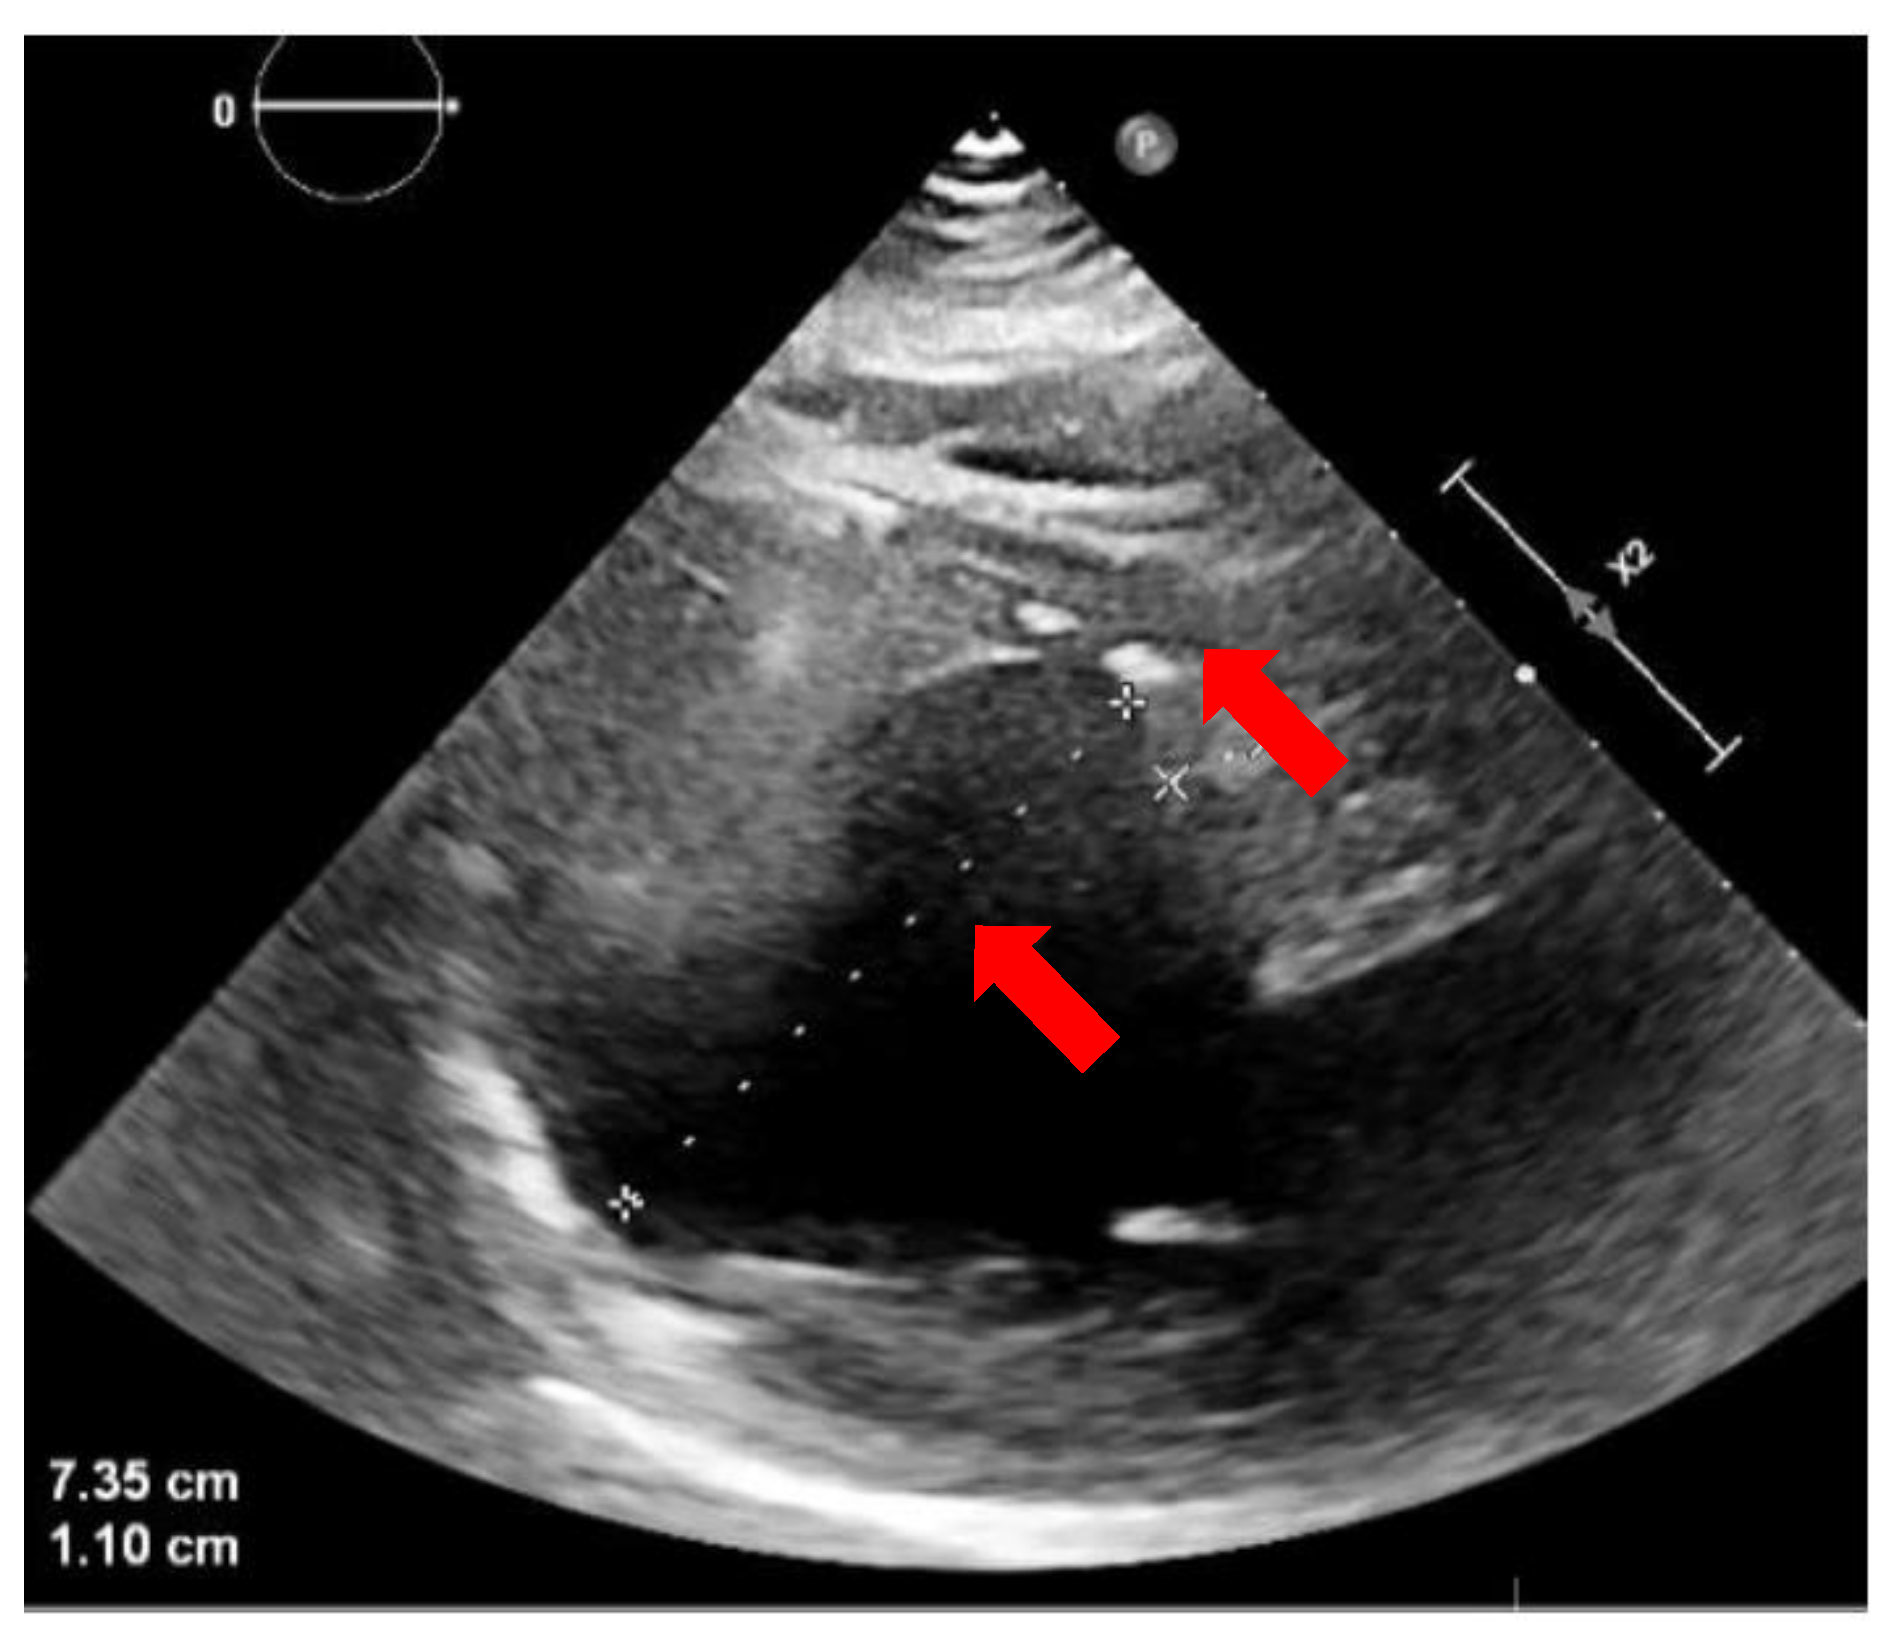

2. Case Presentation